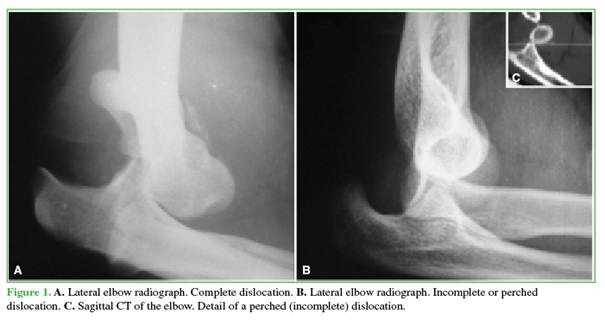

Two classifications guide treatment: simple vs complex (absence or presence of associated fractures) and complete vs incomplete (perched), the latter based on a true lateral radiograph showing the humerus entirely anterior or perched on the coronoid (Figure 1).